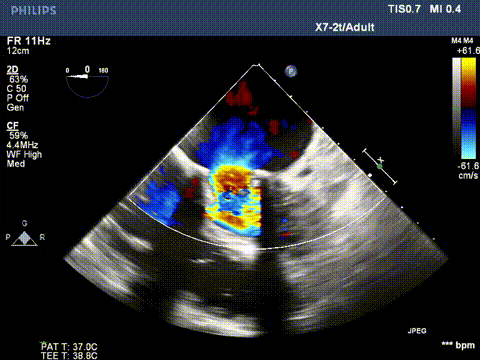

超声显示二尖瓣大量反流

切割前彩超